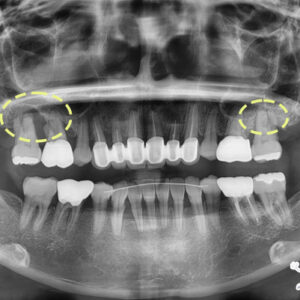

안녕하세요. 반여동치과 스마트치과입니다. 입 냄새, 잇몸 출혈, 치아 시림 등 일상에서 느끼는 다양한 구강 불편의 원인이 생각보다 단순할 수 있습니다. 그 중심에는 바로 ‘치석’이라는 문제점이 자리하고 있습니다. 스케일링은 단순히 치아 표면을 깨끗하게 만드는 처치가 아니라, 입속 건강을 유지하기 위한 가장 기본적인 치료입니다. 특히 일과 생활이 분주한 지역일수록 치과 방문을 미루는 경우가 많은데요, 바쁜 일상 속에서도 정기적인 스케일링은 결코 소홀히 해서는 안 됩니다. 오늘은 스케일링의 중요성과 필요성, 그리고 올바른 관리법에 대해 구체적으로 알아보겠습니다. 스케일링, 단순한 치아 ‘청소’ 그 이상입니다 스케일링은 치아 표면뿐만 아니라 잇몸 경계선 아래에 붙은 더보기…